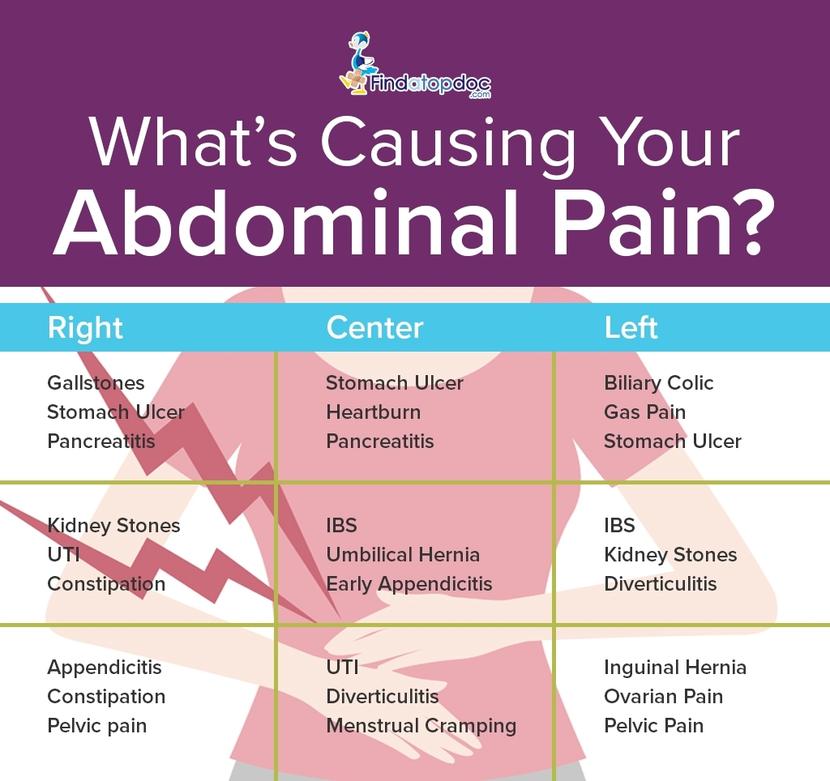

Natural Gas Futures Trading Strategies: Is Gas A Symptom Of Appendicitis

What Does Gas Pain Feel Like? Stomach Upset vs. Gas Pain

Best 25+ Abdominal pain ideas on Pinterest | Stomach pain chart …

5 Causes of gas pain in children – Indian Parenting & Motherhood …